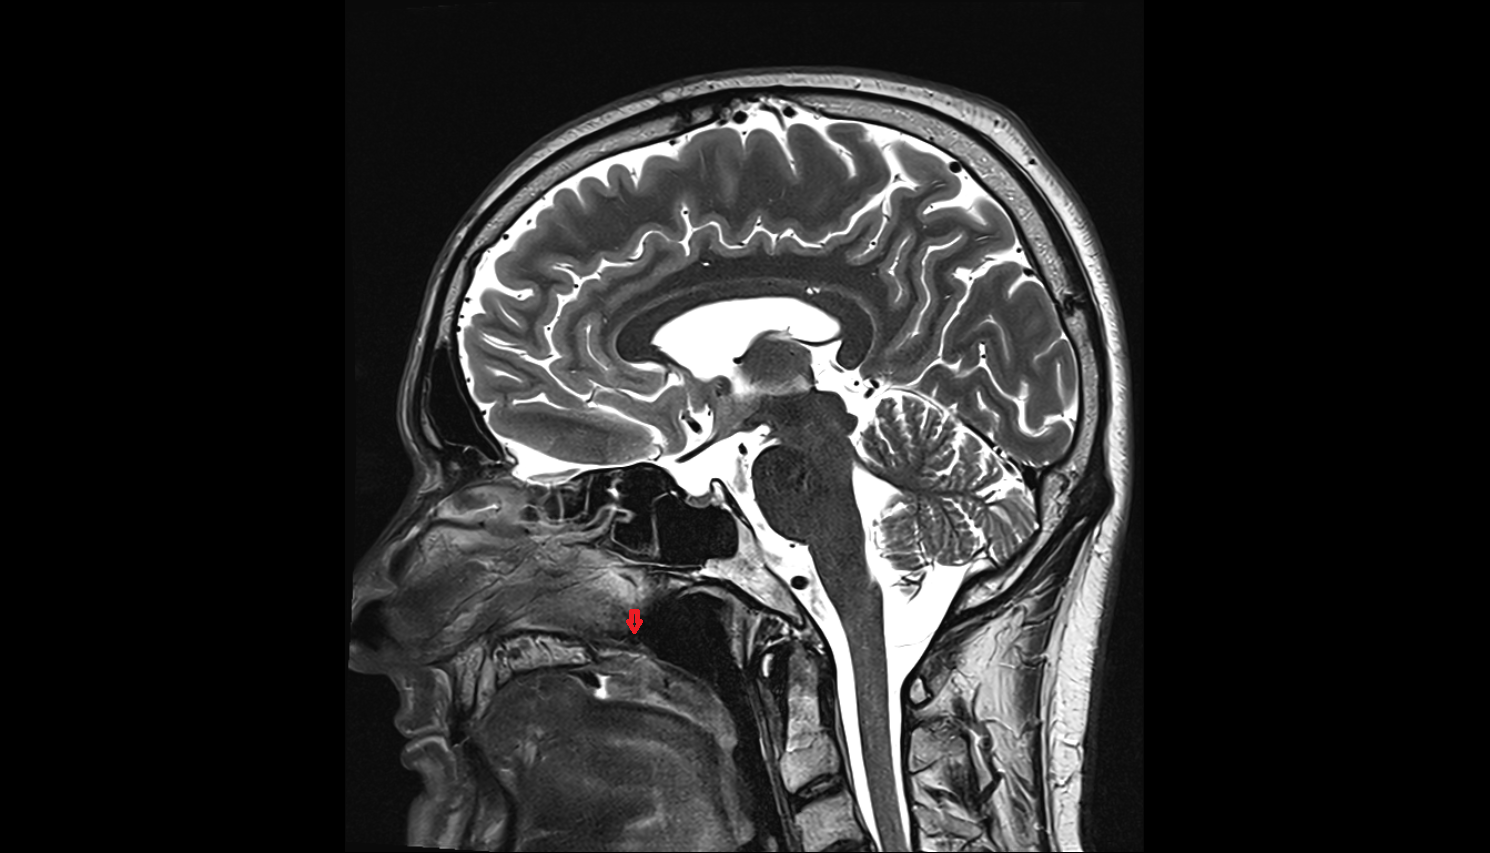

- Pituitary gland

- Pituitary stalk

- Anterior lobe of pituitary gland

- Posterior lobe pituitary gland

- Optic chiasm

- Mammillary body

- Pons